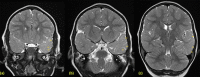

Fig. 2

MRI Brain with coronal oblique T2 images of the temporal lobes from anterior to posterior (a) – (c): There is asymmetric T2 high signal within the left anterior temporal lobe and polar white matter (arrows) consistent with an underlying cortical dysplasia. The hippocampi have a normal appearance. The right temporal lobe myelination is within normal limits for age.